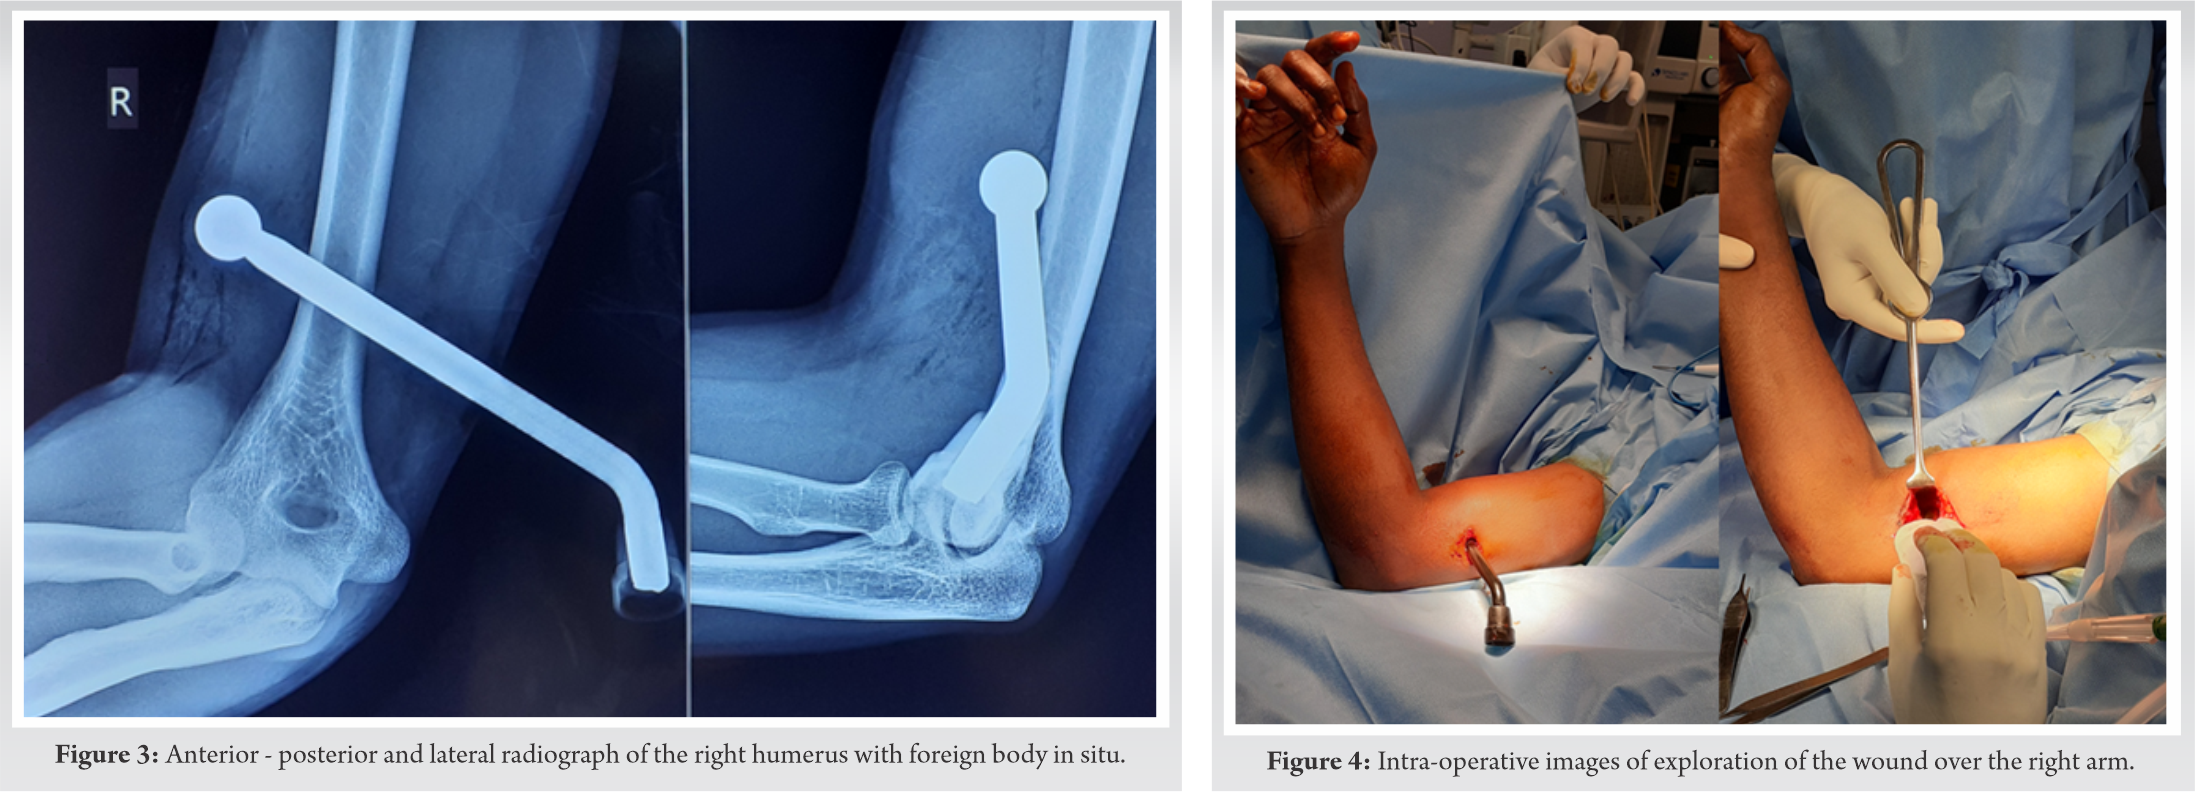

Wrist and finger movements were normal. A radiograph was taken to look for possible foreign bodies (Fig. 3), and it showed a large metallic foreign object plunged into the anterior musculature of the lower third arm with blunt-end in situ. The patient was shifted to the operating room after getting the routine labs done. In the theater, the wound was explored under regional anesthesia (Fig. 4).